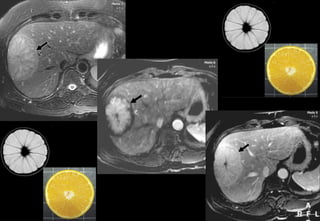

Adénome - IRM

T1 + có tiêm Gadolinium

• Thì sớm

– Ngấm thuốc mạnh

– Không đồng nhất

• Thì muộn

– Có vỏ ++

– Ngấm không đồng nhất

T1 T1 Gado

TruFi STIR

chẩn đoán phân biệt

HNF không điển hình

HCC

CHC xơ